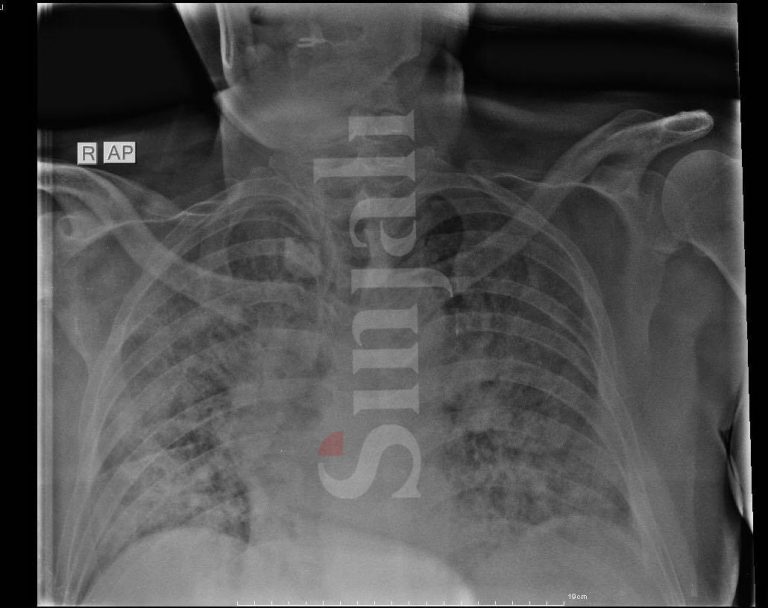

Gazeta Sinjali ka arritur t’i sigurojë Rentgenin e mushkërive të një 63-vjeçari, të cilat ishin të dëmtuara rëndë në më pak se 12 orë.

Fotografia e parë është në momentin kur është pranuar në spital, ndërsa fotografia e dytë është dëmtimi i mushkërive në më pak se 12 orë.